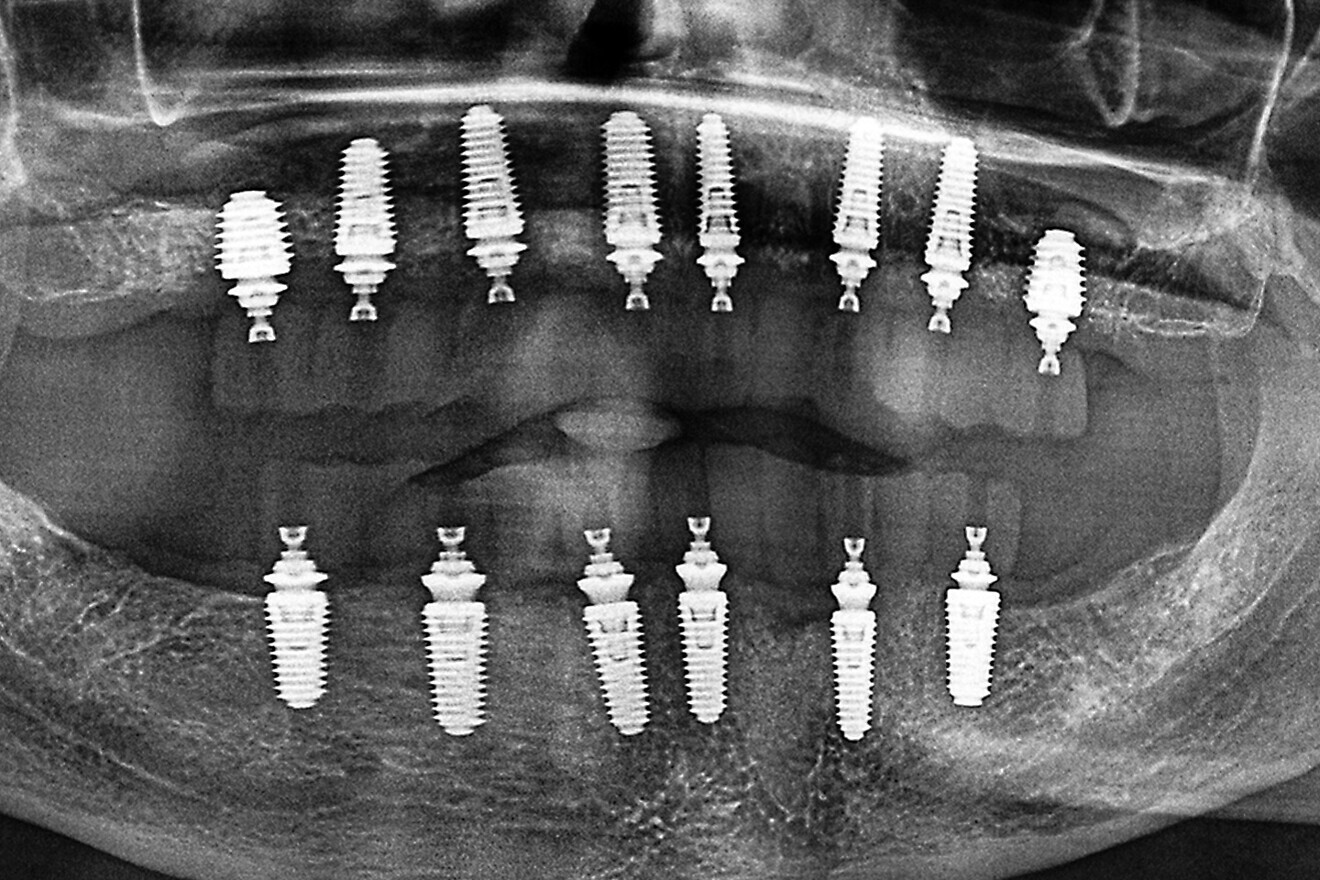

The following case exhibits the features and benefits of utilising Grammetry in combination with innovative screw technology. The 63-year-old male patient with a non-contributory medical history presented with failing dentition in both arches. Diagnostic records were collected, including full-mouth digital radiographs (RVG 6200, Carestream Dental; Fig. 11a), intra-oral scans (Medit i700 wireless; Figs. 11b & c), a large field of view CBCT scan (Carestream 9600; Fig. 11d), and intra-oral and extra-oral photographs (Fig. 11e). The mandible contained an impacted canine as well as several mobile and painful teeth. The maxilla was in a similar condition, having deteriorating, painfully mobile teeth, as well as extensive caries. While the bone loss was significant in the mandible, the vertical dimension of occlusion (VDO) allowed for both arches to be treated with an FP-1 prosthesis.

Fig. 11a: Full-mouth radiograph series revealing caries and periodontal defects.